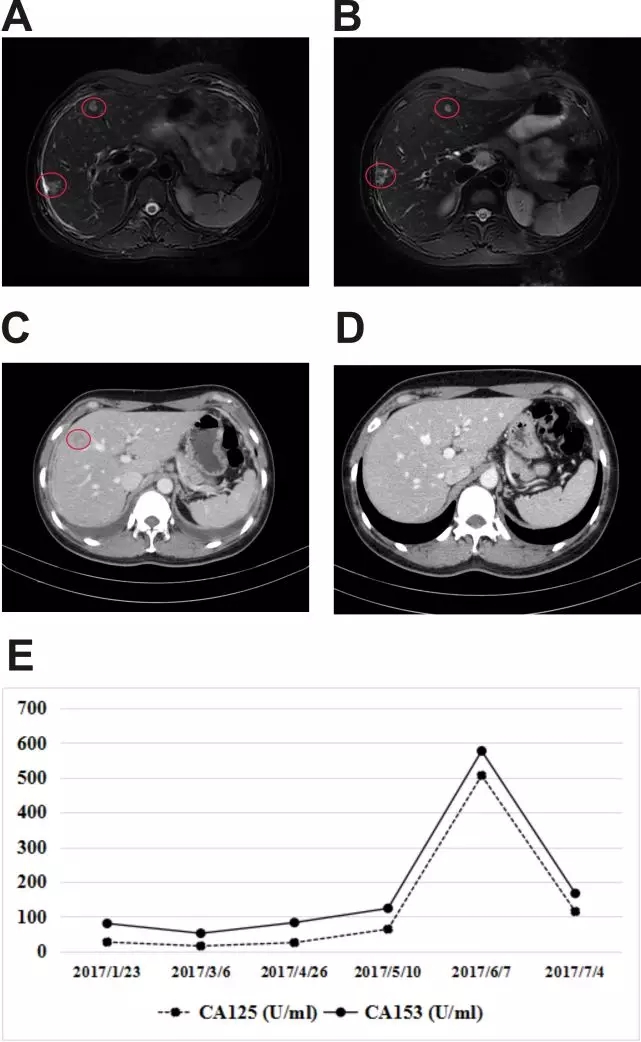

其中有1例HER2扩增患者携带HER2 C.1900 T> C/P.C634R点突变,该患者对曲妥珠单抗和拉帕替尼耐药,而对于不可逆HER2-TKI阿法替尼敏感。另外2例HER2未扩增患者携带HER2点突变接受抗HER2治疗都显示出了相应的疗效。1例患者携带 p.L755_T759del缺失突变,该患者对阿法替尼和曲妥珠单抗都有效。另外1例患者同时携带p.S310F和p.D769Y点突变,该患者从拉帕替尼治疗中获益。